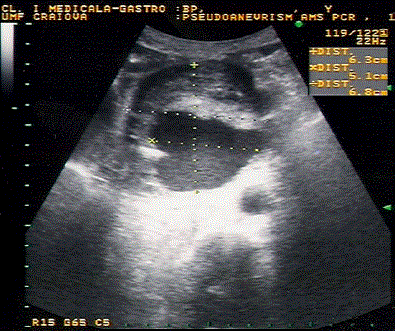

Figure 2. Gray-scale ultrasound showing a large pseudocyst in the pancreatic head with spinning spontaneous contrast inside visualized on tissue harmonic imaging (see videoclip of Movie 1 [www.joplink.net/prev/200501/02_v1.avi]).